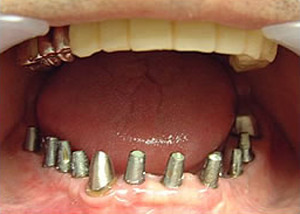

下はチタンの土台が10本入りました。

15.下の土台は平行性あわせて削ったところです。

17.下の仕上がり上部構造3ケに分かれているが、入ると一体化します。

18.3ケのパーツが一体になりました。

19.下は作った最終本物の歯が入りました。